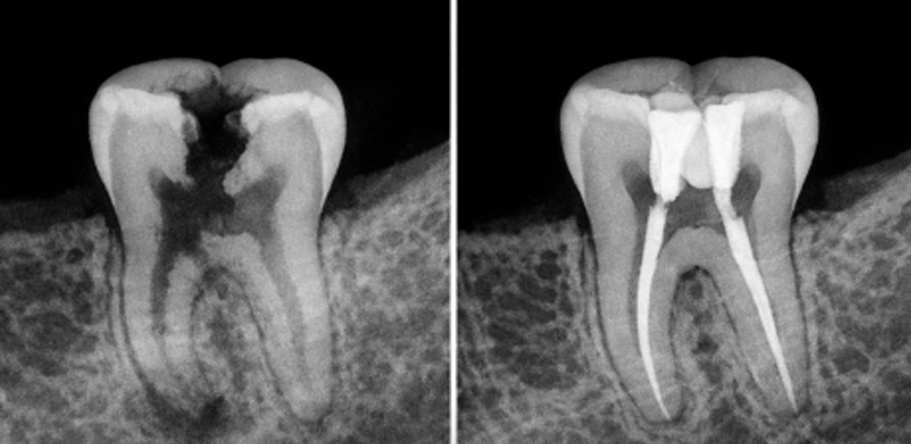

Es un procedimiento dental diseñado para tratar infecciones o daños dentro de un diente. Implica la extracción de la pulpa dental (el tejido blando dentro del diente que contiene nervios y vasos sanguíneos), seguido de la limpieza, desinfección y sellado de los conductos radiculares. Este tratamiento es recomendado cuando la caries esta cerca del nervio y es necesario cuando la pulpa se daña o se infecta a causa de caries profundas, su objetivo es salvar el diente y prevenir su extracción.

La infección puede empeorar y propagarse al hueso circundante u otras partes del cuerpo.

Retrasar el tratamiento puede llevar a procedimientos más costosos y complejos, como implantes o puentes.